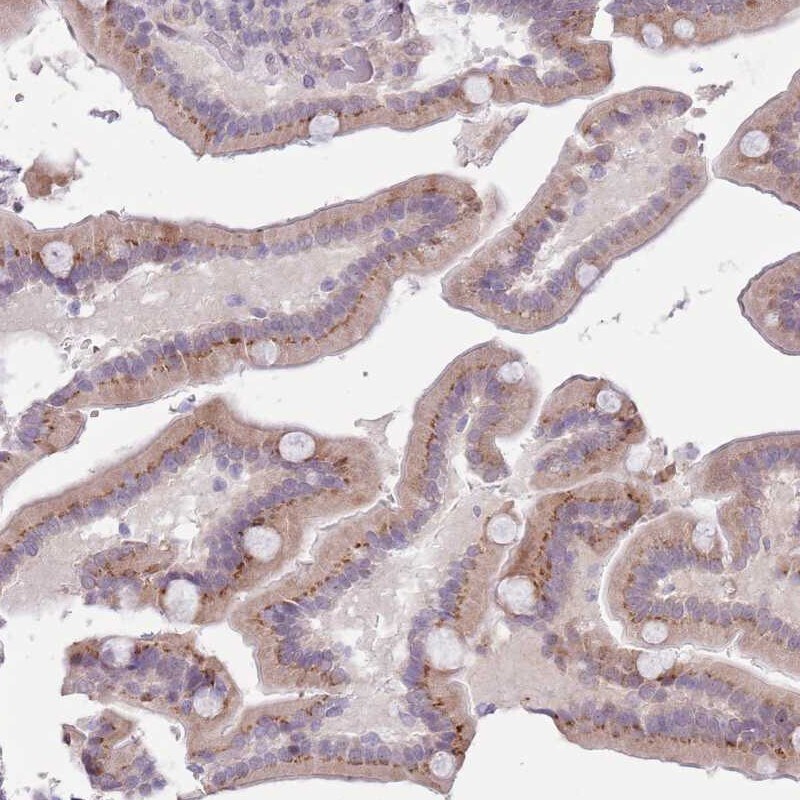

- Submitted by

- Invitrogen Antibodies (provider)

- Main image

- Experimental details

- Immunohistochemical analysis of ZN576 in human duodenum using ZN576 Polyclonal Antibody (Product # PA5-62128) shows moderate cytoplasmic positivity in glandular cells.